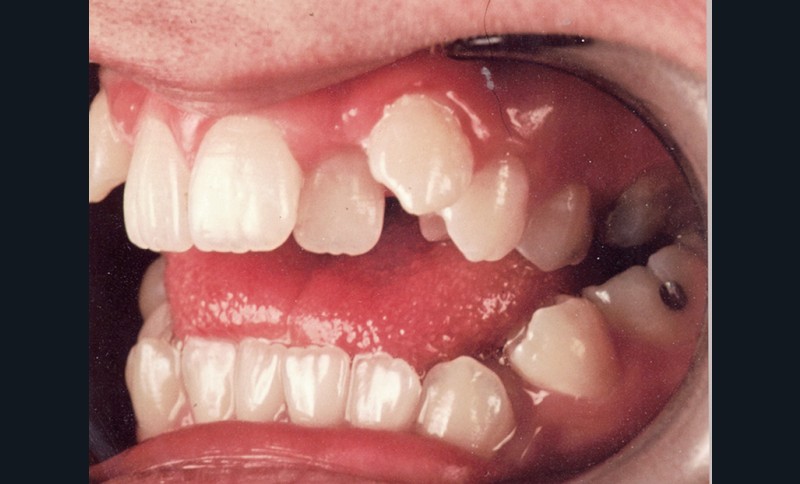

Au niveau squelettique, elle présente une classe I associée à une endognathie maxillaire et une hyperdivergence mandibulaire majeure liée à un excès de croissance alvéolaire verticale postérieure maxillaire et une inclinaison mandibulaire très marquée (fig. 1 et 3).

Sur le plan occlusal et dentaire, on observe une classe I molaire, une occlusion transversale en bout à bout à droite et inversée à gauche et une béance antérieure sévère s’étendant jusqu’aux molaires. Un encombrement est présent aux deux arcades avec des dystopies canines importantes (fig. 2).